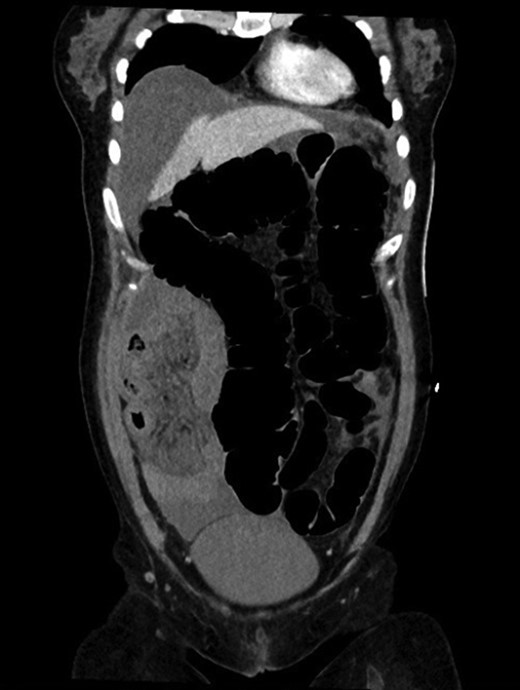

Colonoscopy revealed melanosis coli, diverticulosis and grade four hemorrhoids. She was admitted overnight following haemorrhoidectomy. The following morning she complained of abdominal pain, which she described similar to diverticulitis, and she was tender on exam. To rule out perforation, a plain film abdomen was performed. Findings were suggestive of gaseous distension following colonoscopic air insufflation without evidence of free gas (Fig. 1). Watchful waiting approach was adopted, however the patient deteriorated further during the course of the day. She had a vasovagal episode with tachycardia (134 bpm) and hypotension (67/47 mmHg). A venous blood gas revealed lactate level of 7 mmol/l. She underwent an urgent CT with findings suggestive of pericaecal internal hernia with the ileal loops located in the right paracolic gutter demonstrating features of ischemia (Fig. 2). There was moderate amount of free fluid, but no free gas to suggest perforation (Fig. 3). She was taken to theater that day for emergency laparotomy. The intraoperative findings included two litres of bloodstained fluid and floppy cecum with a band of adhesion to its own mesenteric base, probably adhesional having developed after the appendicectomy. This band has created a window through which three quarters of her small bowel had herniated and became strangulated. The bowel looked very ischemic, but not necrosed. The surgeons divided the adhesion, untwisted the small bowel and waited 20 minutes to allow sufficient time for bowel ischemia to recover. Fortunately, she did not require any bowel resection.

CT coronal view showing pericaecal internal hernia of ileal loops demonstrating features of ischemia.